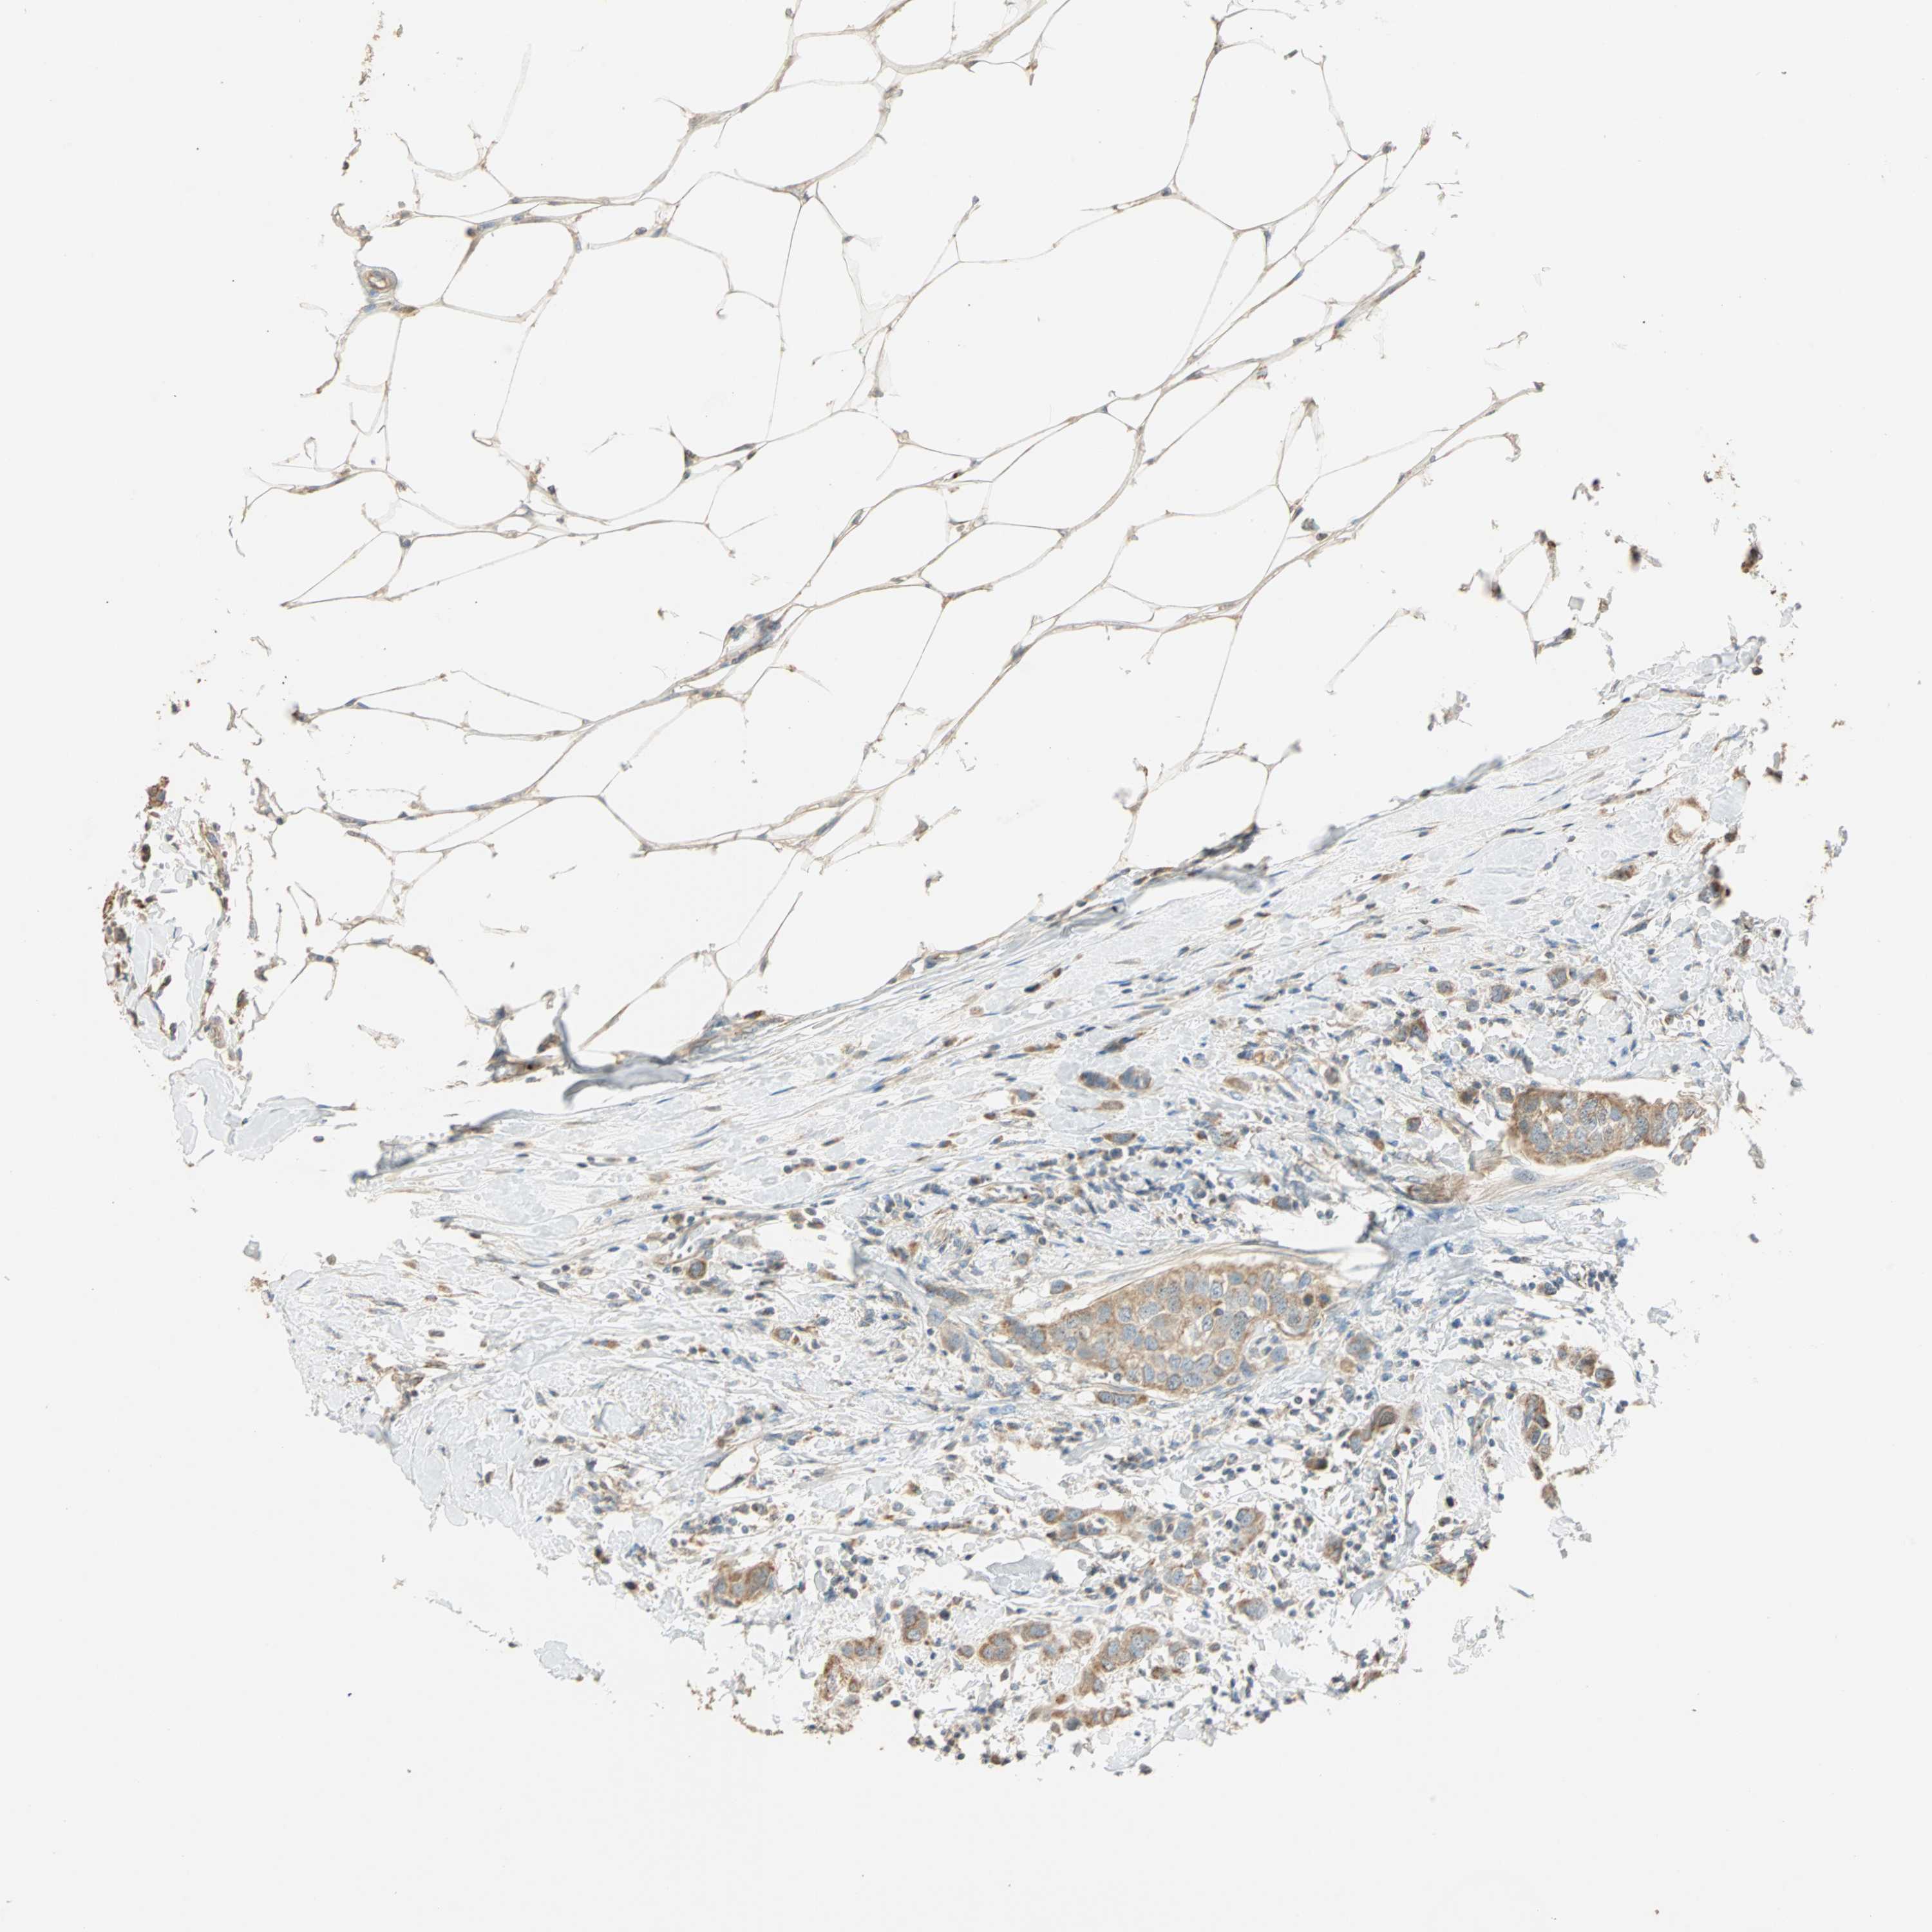

CANCER BREAST CANCER Show tissue menu

BRCA TCGA BRCA VALIDATION PROTEIN EXPRESSION

Breast cancer

Human cancer

Breast invasive carcinoma